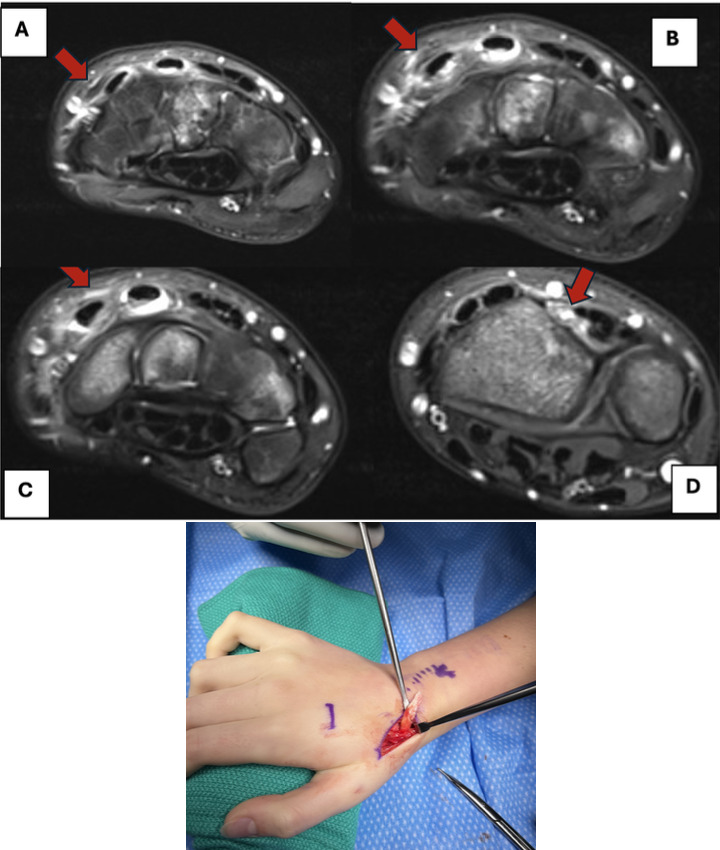

He subsequently underwent repeat closed reduction and percutaneous pinning. [Figure 4] Percutaneous pins were removed at three weeks, and the patient was fitted with a cock-up wrist splint to wear at school and was advised to remain out of sports. At the final follow-up one month later, the patient denied any pain and showed a full range of motion of the right wrist compared to the contralateral side. X-rays confirmed the healing of the fractures, and the patient was cleared for normal activity.